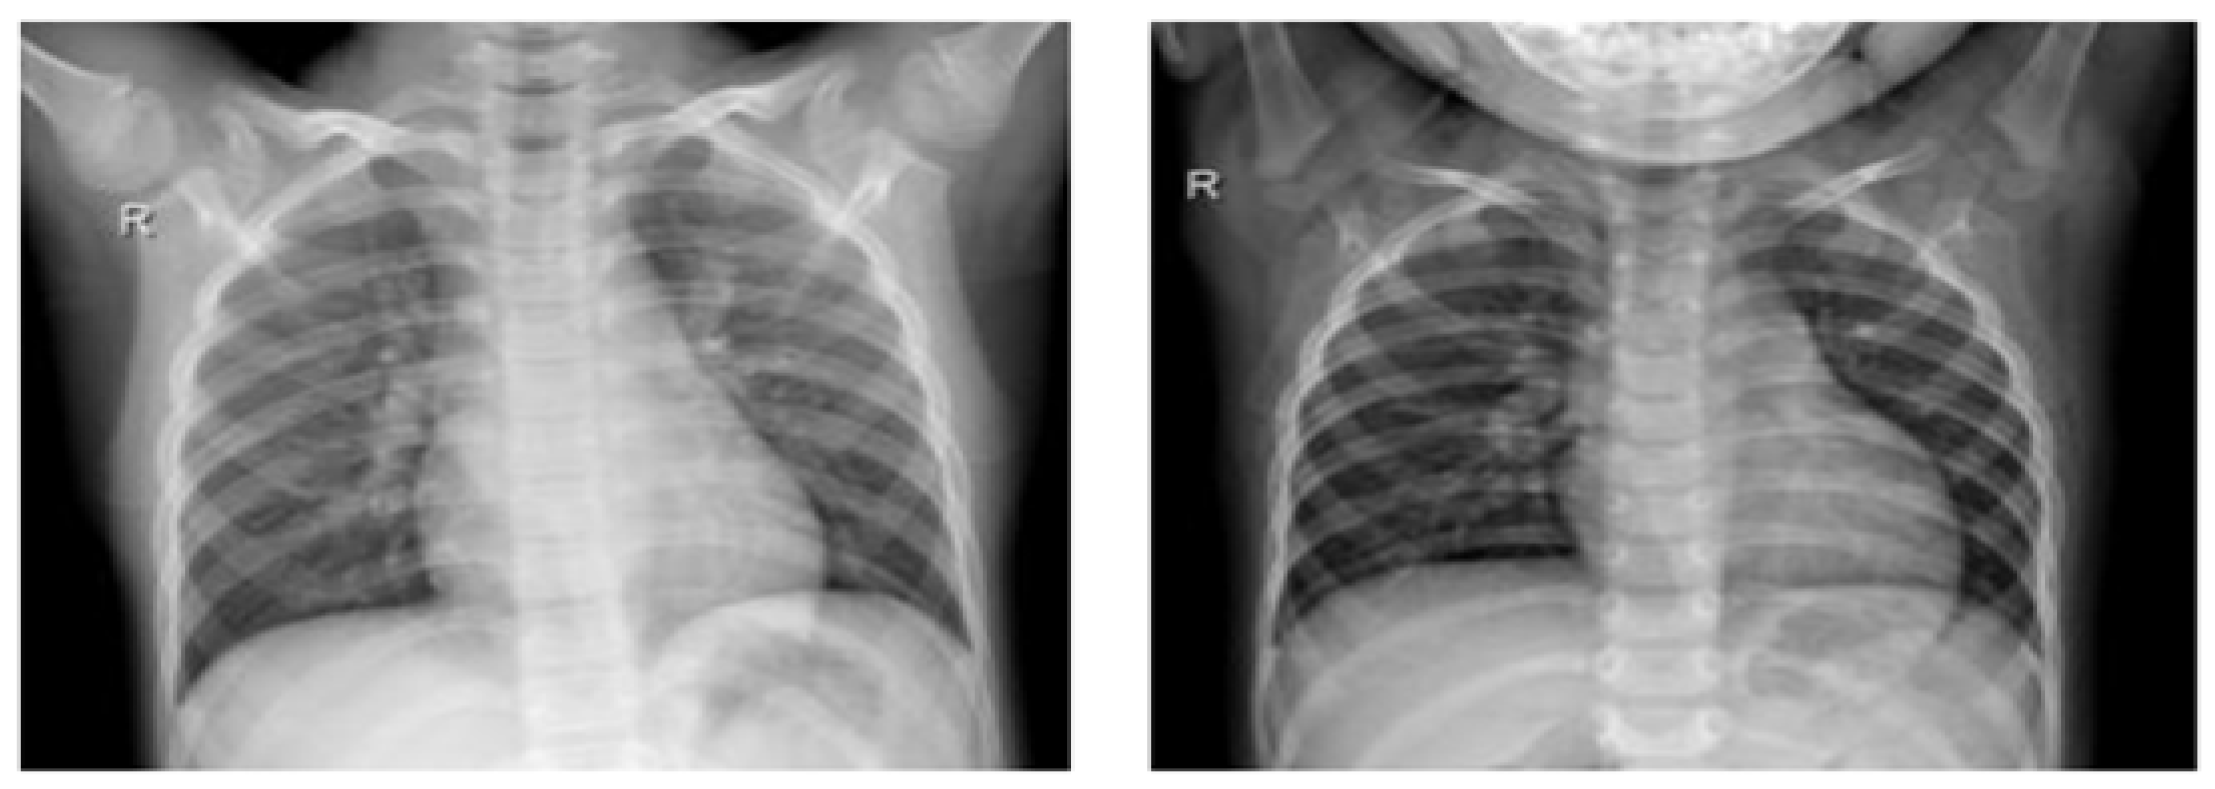

The evaluation framework known as the ImageNet Large Scale Visual Recognition Challenge (ILSVRC) serves as a robust assessment tool for large-scale object detection and image categorization methods (Figure 3). One overarching goal of this framework is to facilitate a broader comparison of progress in object detection across a diverse spectrum of objects, effectively leveraging the considerable effort invested in labeling tasks. The extensive ImageNet dataset comprises a staggering 14,197,122 images, meticulously labeled according to the WordNet hierarchy. Since its inception in 2010, this dataset has served as the cornerstone of the ImageNet Large Scale Visual Recognition Challenge (ILSVRC), an esteemed benchmark for image classification and object recognition. The publicly accessible dataset features images that have undergone meticulous manual annotation. Moreover, a subset of test images intentionally excludes these manual annotations, enhancing the rigor of the benchmark. ILSVRC annotations assume two primary forms: Firstly, image-level annotations capture binary labels indicating the presence or absence of an object class within an image. For instance, these annotations might convey the message “this image contains cars” while simultaneously noting “there are no tigers present”. Secondly, object-level annotations offer comprehensive bounding boxes and class labels for individual object instances in images. These meticulous annotations enhance the benchmark’s ability to address both image and object-level recognition challenges.

Figure 3.

Samples of normal X-ray images [4].

The collection of chest X-rays from patients with COVID-19 was sourced from an open-access data repository. This database encompasses a comprehensive set of chest X-ray images, comprising 1184 images of individuals confirmed as COVID-positive and 1319 images of individuals without COVID-19 diagnosis. Our investigation is fundamentally grounded in this database, which organizes chest radiography images into two distinct categories, as visually represented in Figure 4. The categories include individuals who exhibit no infection and individuals who have been diagnosed with COVID-19. To facilitate our research and maintain robust evaluation practices, we randomly partitioned this dataset into two distinct subsets. The division allocated 80% of the images for the training phase, enabling model development and refinement, while the remaining 20% were reserved for testing, serving as an independent validation dataset. This partitioning strategy ensures a reliable assessment of our models and their generalization capabilities.

Figure 4.

Sample of infected X-ray images [4].